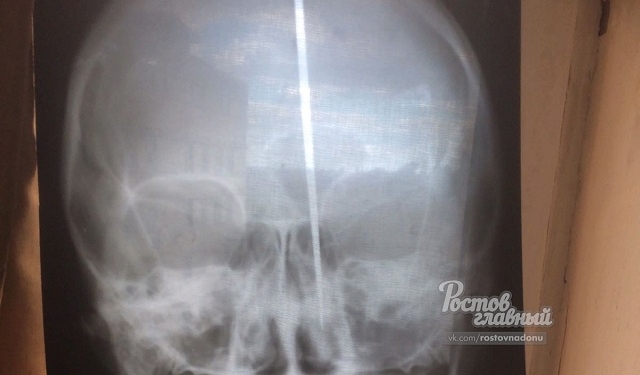

В российском городе Ростов мужчина воткнул себе в голову нож и выжил. Более того он даже смог назвать свои паспортные данные. Нож прошел сквозь весь череп, но мужчина был в сознании.

Свой поступок он объяснил тем, что «голова хотела дышать», сообщает УНИАН.